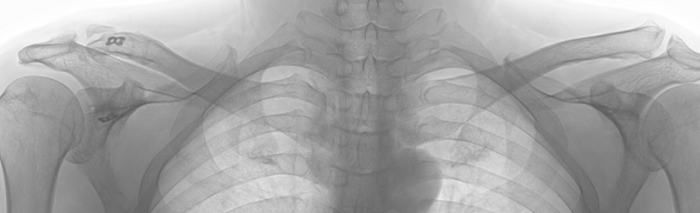

This X-ray was taken when he first came to my clinic in 2018. This shows dislocations of the right acromioclavicular. He also had pains on the shoulder when raising arms. In addition, he felt stiffness and discomfort on the neck, shoulder, and scapular.